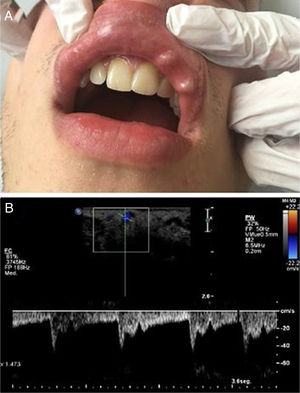

A 25-year-old male with a nibbling habit had been aware of a slowly enlarging reddish-blue, translucent, and pulsatile nodule of the right side of his lower lip of 7 mm. He also refers history of recurrent microulcerations in lower lips for years. Color Doppler and spectral curve confirmed the suspicion of CPLA (Fig. 2).

(a), Clinical photograph showing an enlarging reddish-blue, translucent, and pulsatile nodule of the right side of the lower lip of 7 mm. (b), Simultaneous spectral and color analysis using Doppler ultrasound show a high resistance forward flow in a large-diameter inferior labial artery branch at the lower lip.